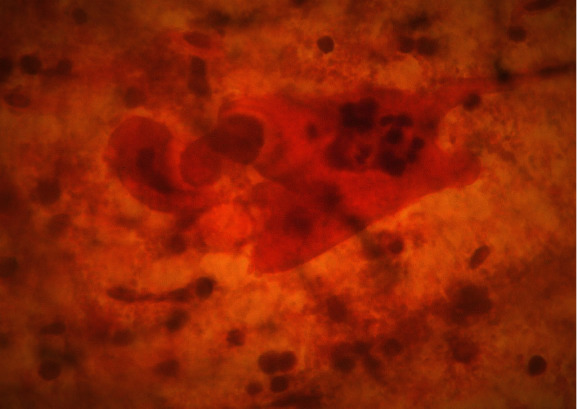

On speculum examination, the outer two-thirds of the vagina and the cervix at the site of the transformation zone appeared normal. However, at the posterior fornix of the vagina, a “discolored area” was seen, extending to the cervix but not reaching the transformation zone and the cervical orifice. There were no obvious signs of laceration, bleeding, or neoplastic erosion of the epithelium. However, it drew the clinical suspicion of the attending gynecologist as an “atypical lesion” which necessitated further thorough evaluation (Figure 1). The impression at first was of an “enlarged/stony cervix at the bimanual examination,” mimicking a common benign condition such as a cervical fibroid. For completion purposes, a TVS was performed. Analogously with the speculum inspection, TVS revealed at the site of the “discolored lesion” a hyperechogenic area and the relevant acoustic shadow was depicted (Figure 2). At the same visit, samples were taken for cytological examination, including smears from the cervical OS, aimed at evaluating the transformation zone, and smears from the site of the lesion. According to the cytological report, the cytological sample reflected “infiltration of the cervix by lymphoblastic cells” (Figures 3–7).

Figure 3.

Pap smear.